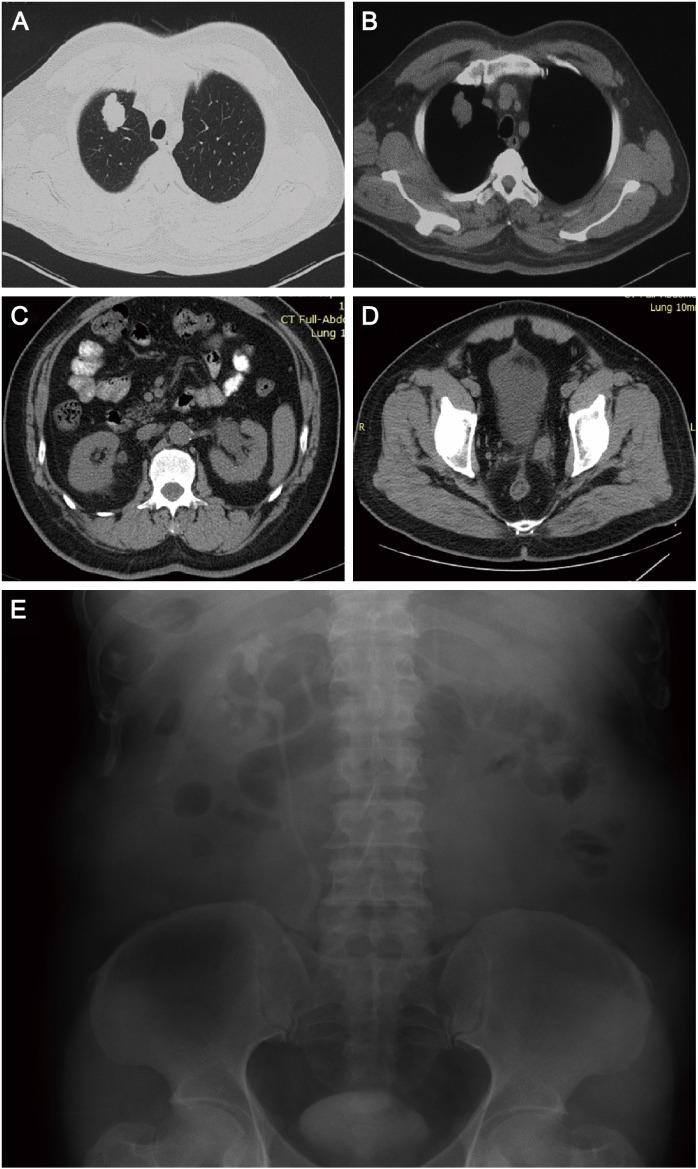

Lung cancer is one of the most common causes of cancer-related death. Most of them already have distant metastasis at the time of diagnosis, but ureteral metastasis is extremely rare. Herein, we reported a lung cancer patient with a metastatic lesion from lung cancer at the distal end of the ureter. The patient is a 61-year-old male diagnosed with invasive adenocarcinoma after the right upper lobe resection and system lymph node dissection surgery. After 12 months of surgery, during routine physical examination, lower abdominal enhanced computed tomography showed there was a soft mass with uneven continuous enhancement at the distal end of the ureter. After the surgery of ureter, the mass was histologically considered to be a metastatic lesion arising from the primary lung cancer.